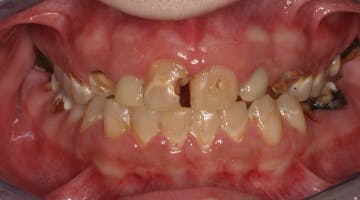

In another example, a young patient had been using e-cigarettes for five years. He started vaping as a method to quit smoking traditional tobacco products thinking vaping was a healthy alternative. Because of its ease of use, he smoked a cartridge of one of the more popular vaping products a day. Admittedly, he also drank energy drinks (high sugar content), stating that his mouth was often dry after vaping. This combination led to rampant decay with smooth-surface lesions and future tooth loss (figure 3).

Figure 3: Effects of e-cigarettes